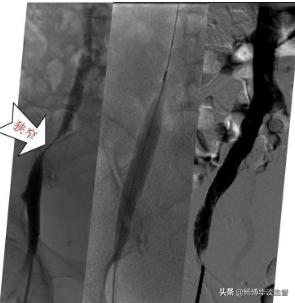

如果一条腿肿,另一条腿正常,这种更多见于静脉血栓性疾病,有一定的危险性,建议到血管外科就诊。深静脉血栓形成一般突发肿胀伴有疼痛,有血栓脱落肺栓塞致死的风险,到血管外科开个下肢深静脉彩超就可以确诊。【病例 1】去年年底,来了一位 86岁老太太,就是因为右边腿肿的特别厉害,已经严重影响到走路,我们给老人做了检查后发现竟然是髂静脉狭窄,我们给予球囊扩张+支架成形术,术后下肢肿胀明显改善!(见下图)